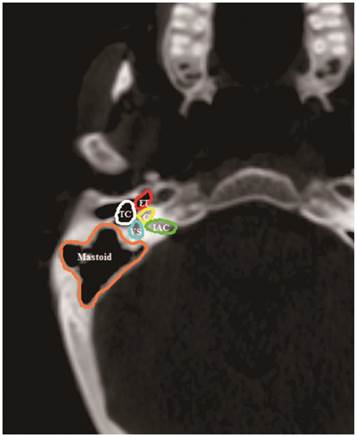

The volumes of the components of the auditory apparatus: the Eustachian tube (ET), tympanic cavity (TC), mastoid air cells, vestibular apparatus (VS), cochlea and internal auditory canal (IAC) were contoured on every slice by a radiation oncologist. Based on anatomic definitions, a reasonable contouring method for the auditory apparatus (Figure 1) was employed11. Dose-volume histograms (DVH) were generated to determine the mean dose to each component of the auditory apparatus. Additionally, one treatment-related variable (concurrent chemotherapy) and patient-related variables (age, patient sex, T classification, N classification and pathologic features) were included as clinical variables. A total of 13 variables were reviewed.

Figure 1

CT anatomy of the Eustachian tube (ET), tympanic cavity (TC), mastoid air cells (Mastoid), vestibular apparatus (VS), cochlea (C), and internal auditory canal (IAC).